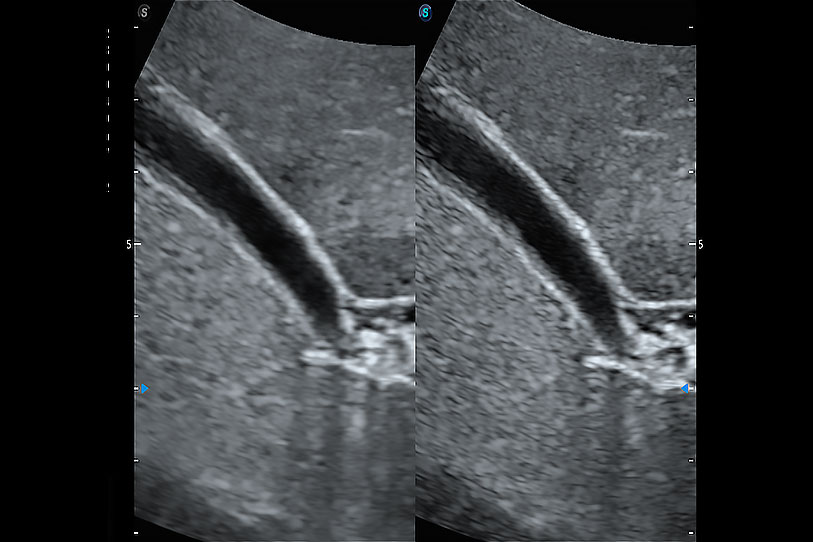

增強(qiáng)穿刺針在動物解剖結(jié)構(gòu)中的位置,提高穿刺介入的安全性和準(zhǔn)確性。

通過色彩血流和實(shí)時(shí)寬景相結(jié)合,可觀察到完整的靜脈或動脈的血流,方便醫(yī)生檢查。實(shí)時(shí)掃查過程中,如有任何操作失誤也可以很容易地進(jìn)行回掃擦除,而不會中斷掃查。